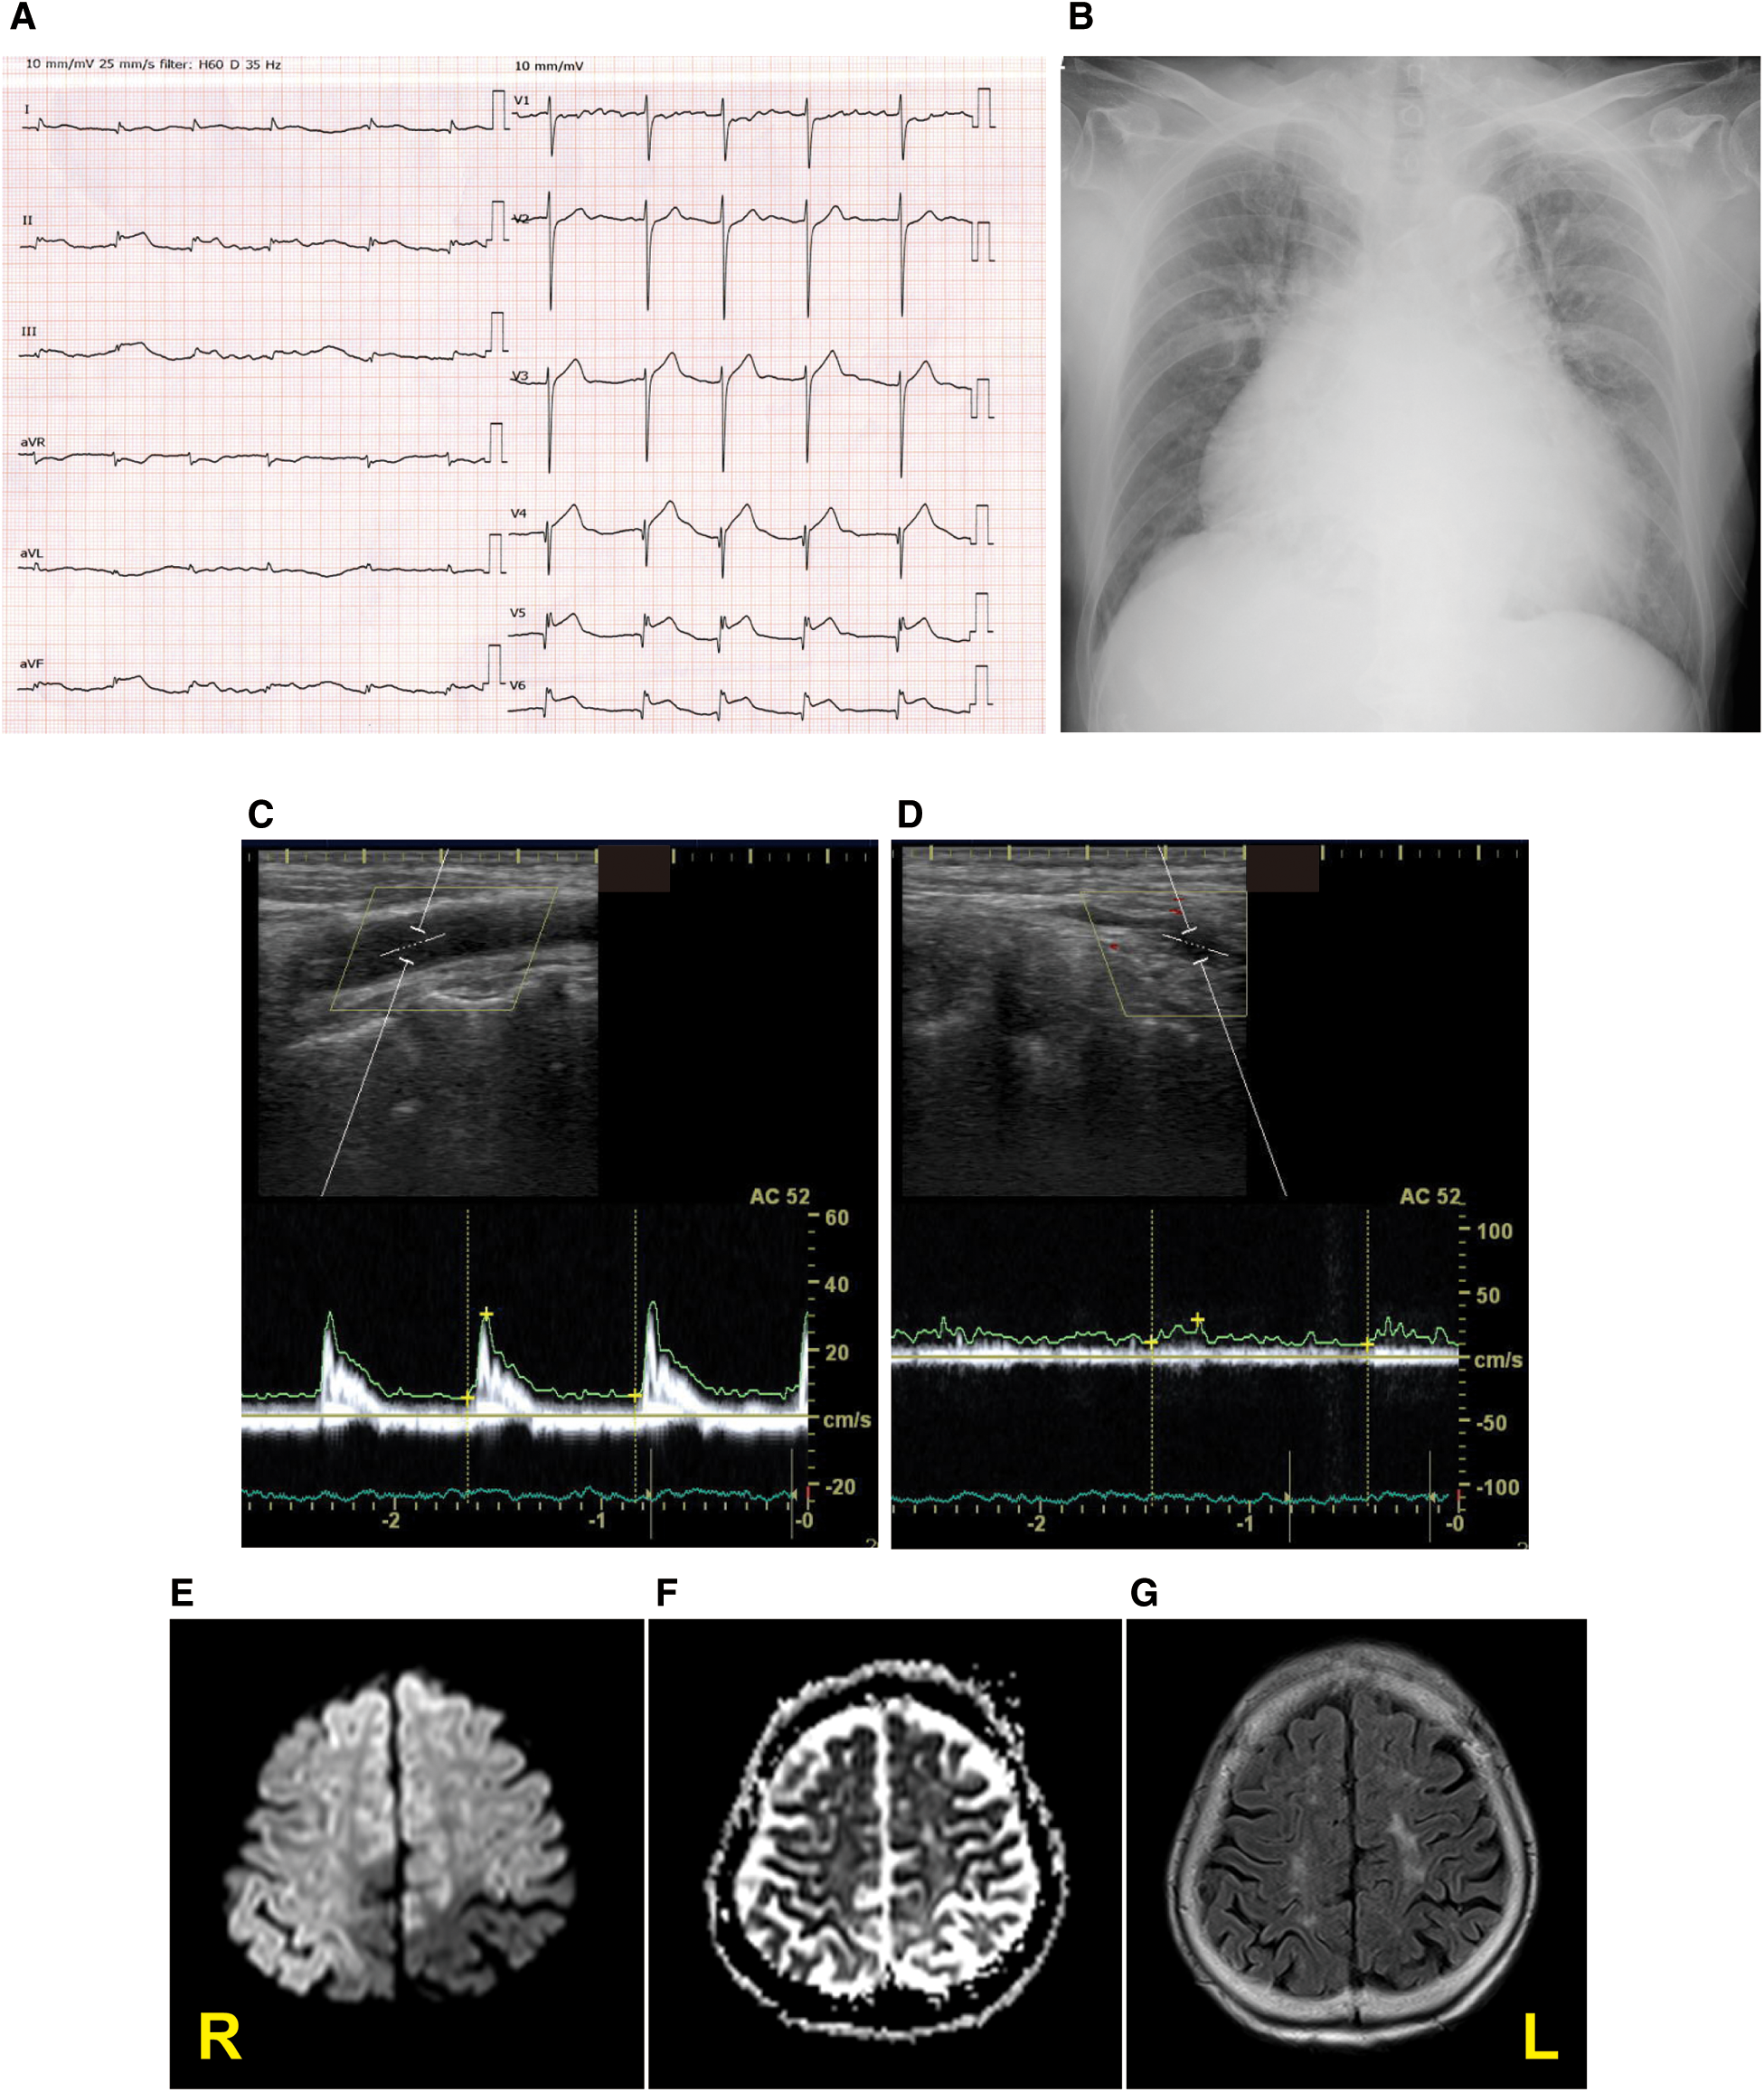

A 92-year-old woman presented to our emergency room with a sudden-onset coma. A family member witnessed that she suddenly fell down on the floor while they were talking. Her eyes were closed, and she had lost consciousness. Although her medical history included chronic AF, hypertension, and aortic valve stenosis, but she did not take any anticoagulants. Her blood pressure was 205/102 mmHg. Neurological examination revealed severe disturbance of consciousness. The patient was mute and could not follow any command. Her Glasgow Coma Scale score was 6 (E1V2M3). The pupil size was normal (3/3 mm), and the oculocephalic reflex showed a positive response; however, roving eye movement was noted. This indicated that the cerebral cortex was impaired while the brainstem was functionally preserved. The pupillary light reflex was prompt bilaterally. Motor assessment revealed flaccid tetraplegia, and the Babinski reflex was bilaterally positive. The National Institutes of Health Stroke Scale score was 34. Blood test revealed 7,600/µl in white blood cell, hemoglobin was 13.4 g/dl, aspirate transaminase was 22 IU/L, alanine aminotransferase was 9 IU/L, sodium was140 mEq/L, glucose was 116 mg/dl, serum creatinine was 0.88 mg/dl, C-reactive protein was 0.04 mg/dL, brain natriuretic peptide was1035.5 pg/mL, and D-dimer was 18.5 µg/mL. A chest x-ray showed cardiomegaly, 72.0% in cardio–thoracic ratio, and ECG revealed AF with ST-segment elevation at II, III, aVF and V4–6 (Figures 1A,B). Echocardiography showed hypokinesis of the anterior and inferior walls. Carotid ultrasonography exhibited a reduction in the end-diastolic velocity (right, 4.9 cm/s; left, 6.3 cm/s) and increased pulsatility index (2.2;2.3) at the bilateral common carotid arteries and did not detect pulse-wave Doppler in the bilateral internal carotid artery (ICA), suggesting that the bilateral ICA was occluded (Figures 1C,D). On brain non-contrast magnetic resonance imaging (MRI), diffusion-weighted MRI (Figure 1E) and apparent diffusion coefficient map (Figure 1F) showed almost the same signal intensity in the infarcted lesions of the bilateral ICA territories, whereas fluid-attenuated inversion recovery revealed no such lesions with a high signal intensity (Figure 1G), demonstrating acute cerebral infarction in the bilateral ICA territories with a nearly simultaneous onset. These clinical findings suggested that acute massive ischemic stroke due to near-simultaneous bilateral ICA occlusion occurred. Following admission, we carefully explained to the family members that reperfusion therapy such as the administration of recombinant tissue-type plasminogen activator, or mechanical thrombectomy was not suitable for the massive cerebral infarction because of the risk of hemorrhagic transformation. Moreover, coronary angiography could not be performed because her neurological prognosis was poor, and the condition would unfortunately be irreversible. Accordingly, conservative medical management was recommended. The family members understood our explanations, and agreed on conservative management after deep deliberation. No reperfusion therapy or coronary angiography was performed. On day 3, her right pupil dilated to 4 mm. On day 4, the patient vomited once. Her pupils further dilated bilaterally to 5.0/4.5 mm, and the oculocephalic and pupillary light reflexes were absent. Her blood pressure and heart rate also gradually decreased. Eventually, the patient died on day 4 of hospitalization before the diagnosis was completed (Figure 2). Clinical differential diagnoses included three categories: (i) conditions leading to concurrent cerebral–coronary infarction in which AF could induce both cardioembolic stroke and coronary artery embolism; (ii) cardiac conditions leading to cerebral infarction, such as intraventricular thrombi due to ST-elevation myocardial infarction or takotsubo cardiomyopathy with ST elevation; and (iii) cerebral infarction leading to AMI through brain–heart axis dysregulation (e.g., insular ischemic stroke). Thus, the etiology of the thrombi and the relationship between AIS and cardiac dysfunction with ST-segment elevation were unclear.

Figure 1. Diagnostic testing performed on admission. Twelve-lead electrocardiography (A), chest x-ray (B), pulse-wave carotid ultrasonography with Doppler in the left common carotid artery (C) and internal carotid artery (ICA) (D), and the diffusion-weighted magnetic resonance imaging (MRI) (E), apparent diffusion coefficient map (F), and fluid-attenuated inversion recovery MRI (G) displaying acute bilateral ICA territory infarction. R stands for right; L stands for left.